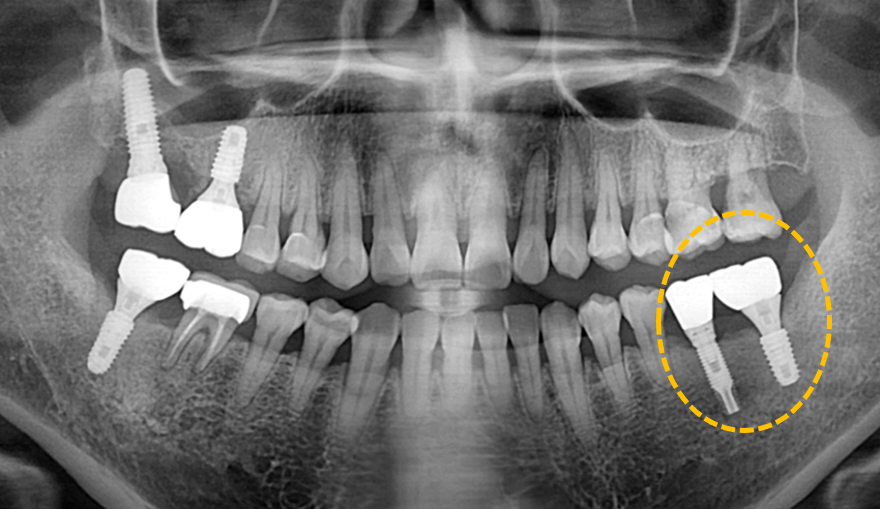

실패한 임플란트 재치료

After

이를 제거하고 새로 임플란트를 식립하여 더욱 이상적인 보철 형태를 만들어 드렸습니다.